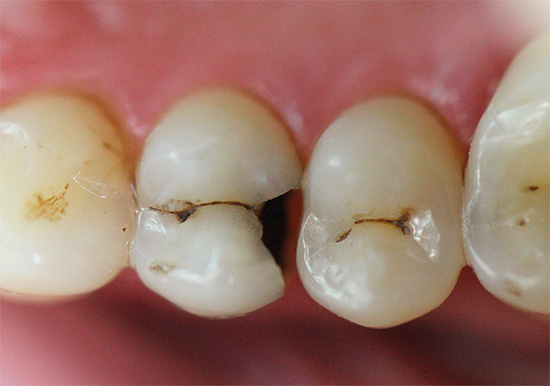

In fasi successive, determinare la carie con un semplice esame è ancora più semplice: porta alla comparsa di punti neri e marrone scuro sui denti o quando la dentina è danneggiata, sotto lo smalto sono visibili cavità scure.

Diagnosi della carie fissurotomica

La fissurotomia consiste nell'aprire lo smalto nell'area delle fessure dei denti per determinare le aree danneggiate dalla carie al di sotto di essa. Naturalmente, in situazioni standard, tale procedura per la diagnosi non viene eseguita: è semplicemente impossibile forare un dente per assicurarsi che sia sano. Di norma, questo metodo viene utilizzato per confermare il sospetto di un medico di carie, nonché per valutare l'entità del danno a un dente cariato.

In generale, questo metodo è principalmente una valutazione della lesione, ma non il rilevamento della carie stessa.

Dallo studio dentistico

Spesso, una parete di contatto con smalto grigio si trova in pazienti su un dente particolare. Sebbene la carie non sia chiaramente visibile, una formazione sconosciuta è visibile sotto lo smalto più intatto. In tutti i casi, dopo l'elaborazione con una fessura o una semplice fresa sferica, lo smalto cade e si apre una vasta cavità nascosta nel dente. Molto spesso, sotto una parete così apparentemente intatta, si sviluppa la polpite cronica.

Carie nelle aree più vulnerabili dei denti - nell'area della fessura